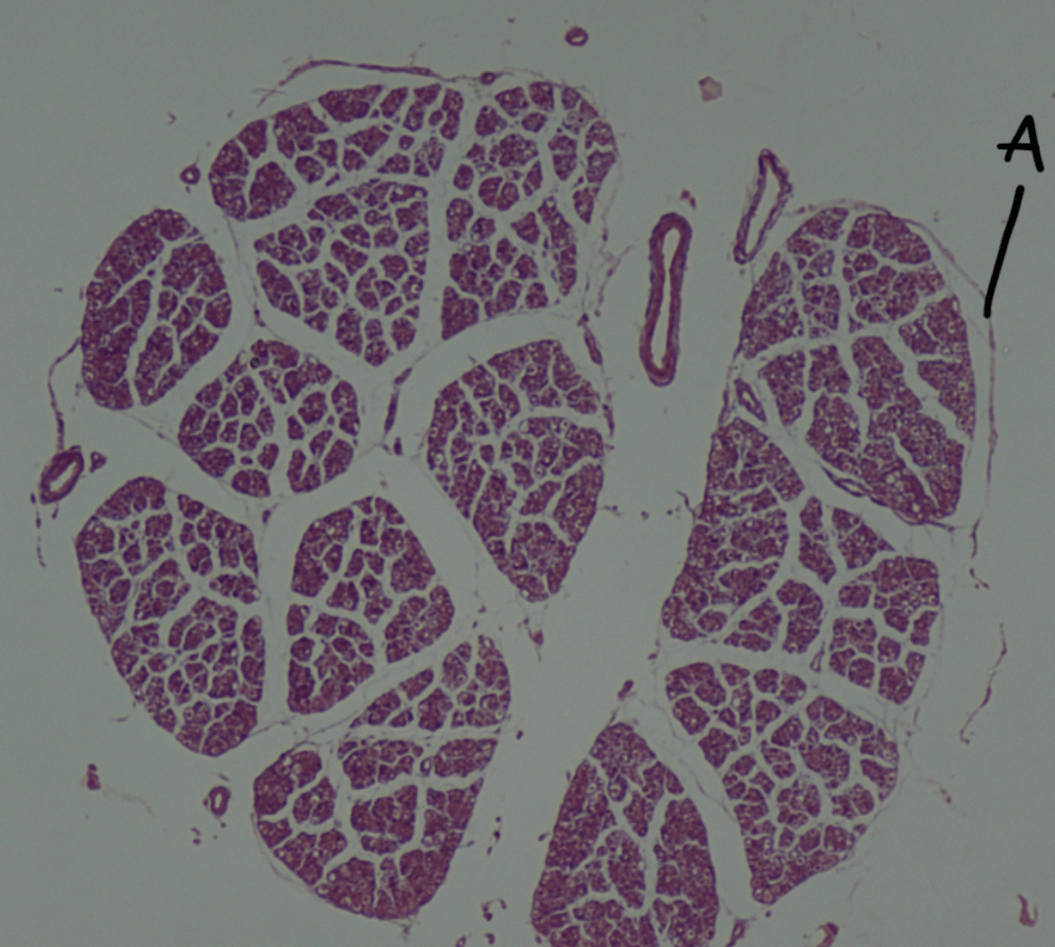

Label A.

Epineurium